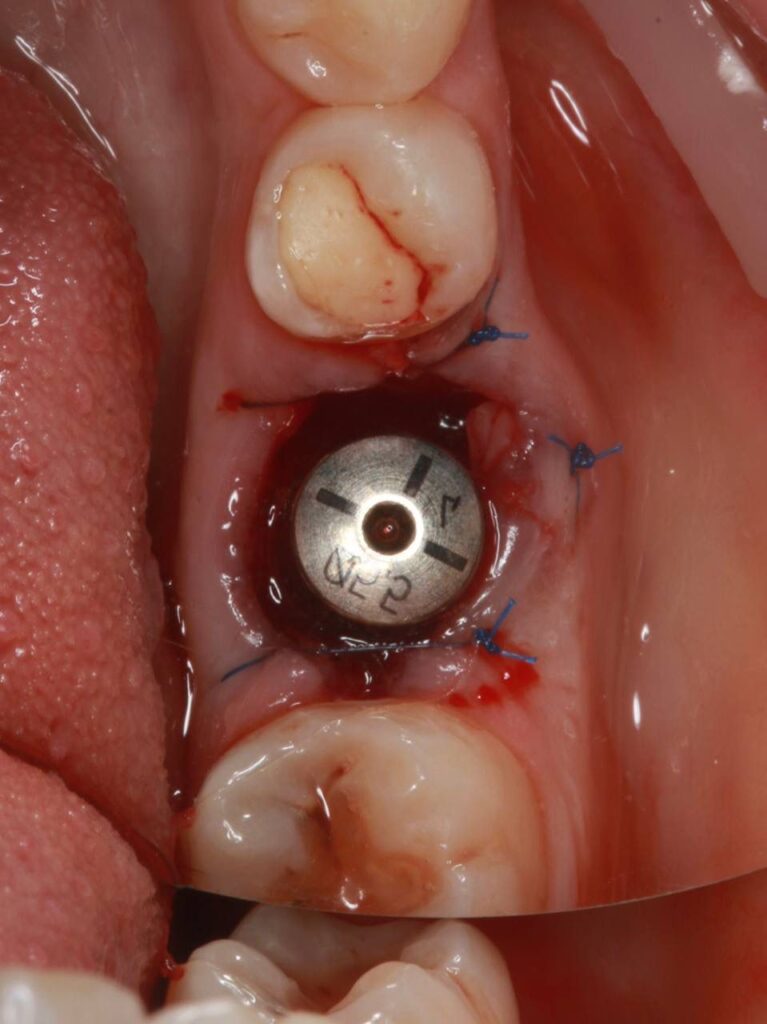

Специализация: терапия(эндодонтия), ортопедия, имплантология.